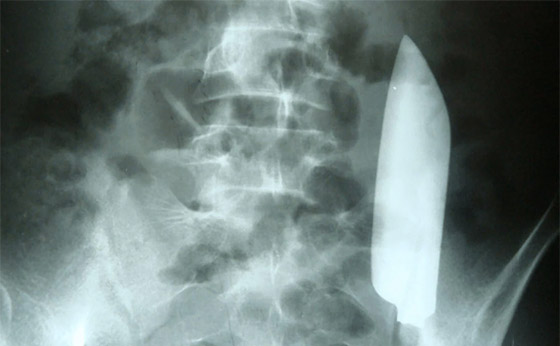

1. العثور على سكين في بطن الرجل

تمت خياطة بطن رجل يبلغ من العمر 22 عاما من نيبال بعد تعرضه للطعن بسكين، ولكن في اليوم التالي علم أن السكين الذي يبلغ طوله نصف قدم تقريبا لا يزال في بطنه. وبعد يوم ذهب إلى قسم الطوارئ لأنه كان يعاني من ألم خفيف ومستمر في أسفل بطنه الأيسر. وقال التقرير الطبي إن الأطباء المذهولين رأوا أن السكين "تجول" في الجانب الآخر من جسد الرجل، ولكن بأعجوبة، حدث ذلك دون الإضرار بأي من أعضائه المحيطة.